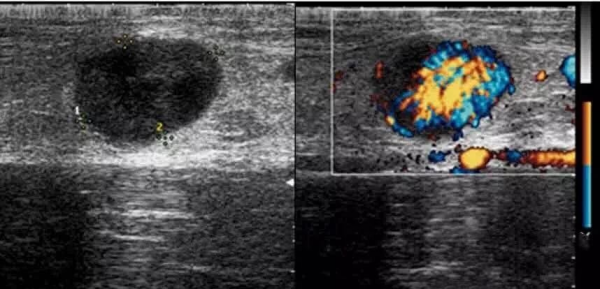

图2 颈部淋巴结肿大的超声表现

引起颈部淋巴结增大的原因很多,例如细菌、病毒的感染,恶性肿瘤的转移、血液系统的疾病、淋巴瘤及一些免疫因素等。常见的良性淋巴结疾病有淋巴结反应性增生、急性/慢性细菌性淋巴结炎、淋巴结核等,另外还有一些少见的良性疾病,如猫抓病、组织坏死性淋巴结炎(Kikuchi)、结节病、巨大淋巴结增生及嗜酸性粒细胞增多性淋巴肉芽肿(木村病)。恶性淋巴结病变以转移性淋巴结及淋巴瘤最为常见。各种病因引起的淋巴结疾病其治疗方法也不相同,故准确地判断肿大淋巴结的性质,有利于对疾病实施尽早的干预治疗。